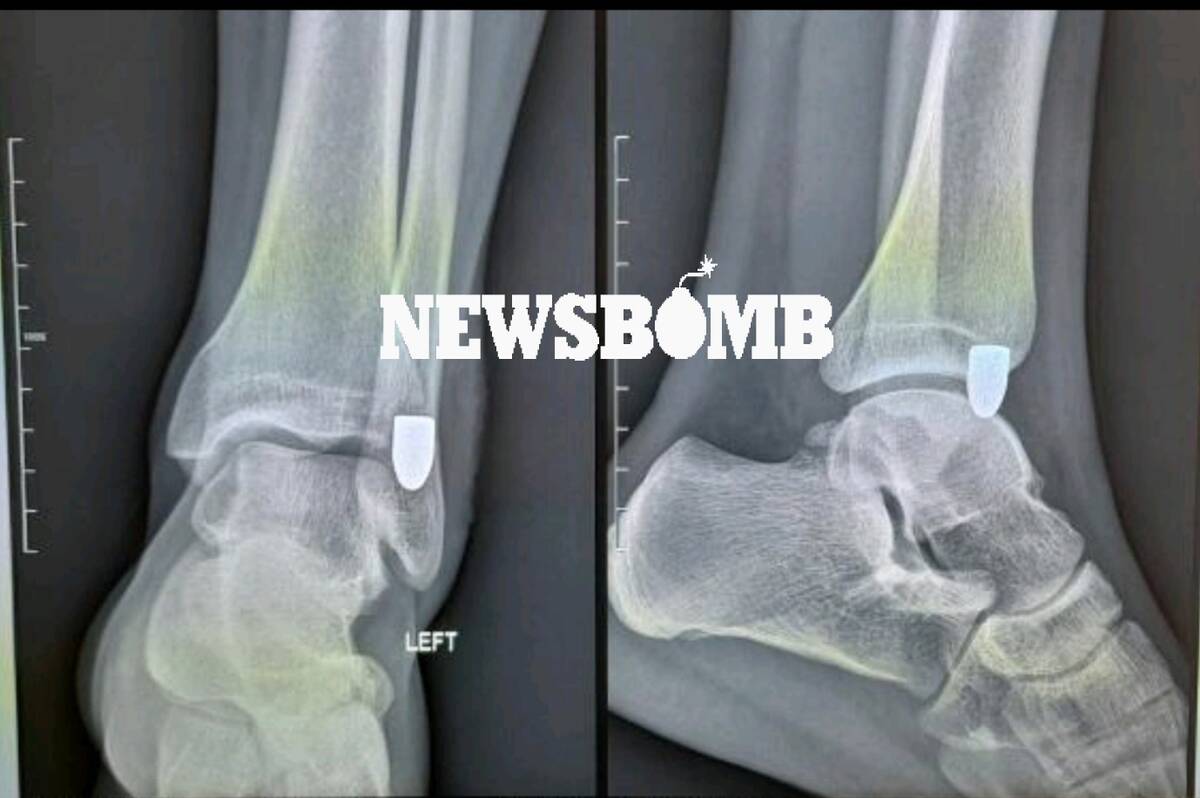

Ο τραυματίας διακομίστηκε στο νοσοκομείο, όπου η ακτινογραφία έδειξε καθαρά την «καρφωμένη» σφαίρα στο πόδι του.

Η ιστοσελίδα, Newsbomb.gr, έδωσε στη δημοσιότητα φωτογραφία από την ακτινογραφία του Δανού.